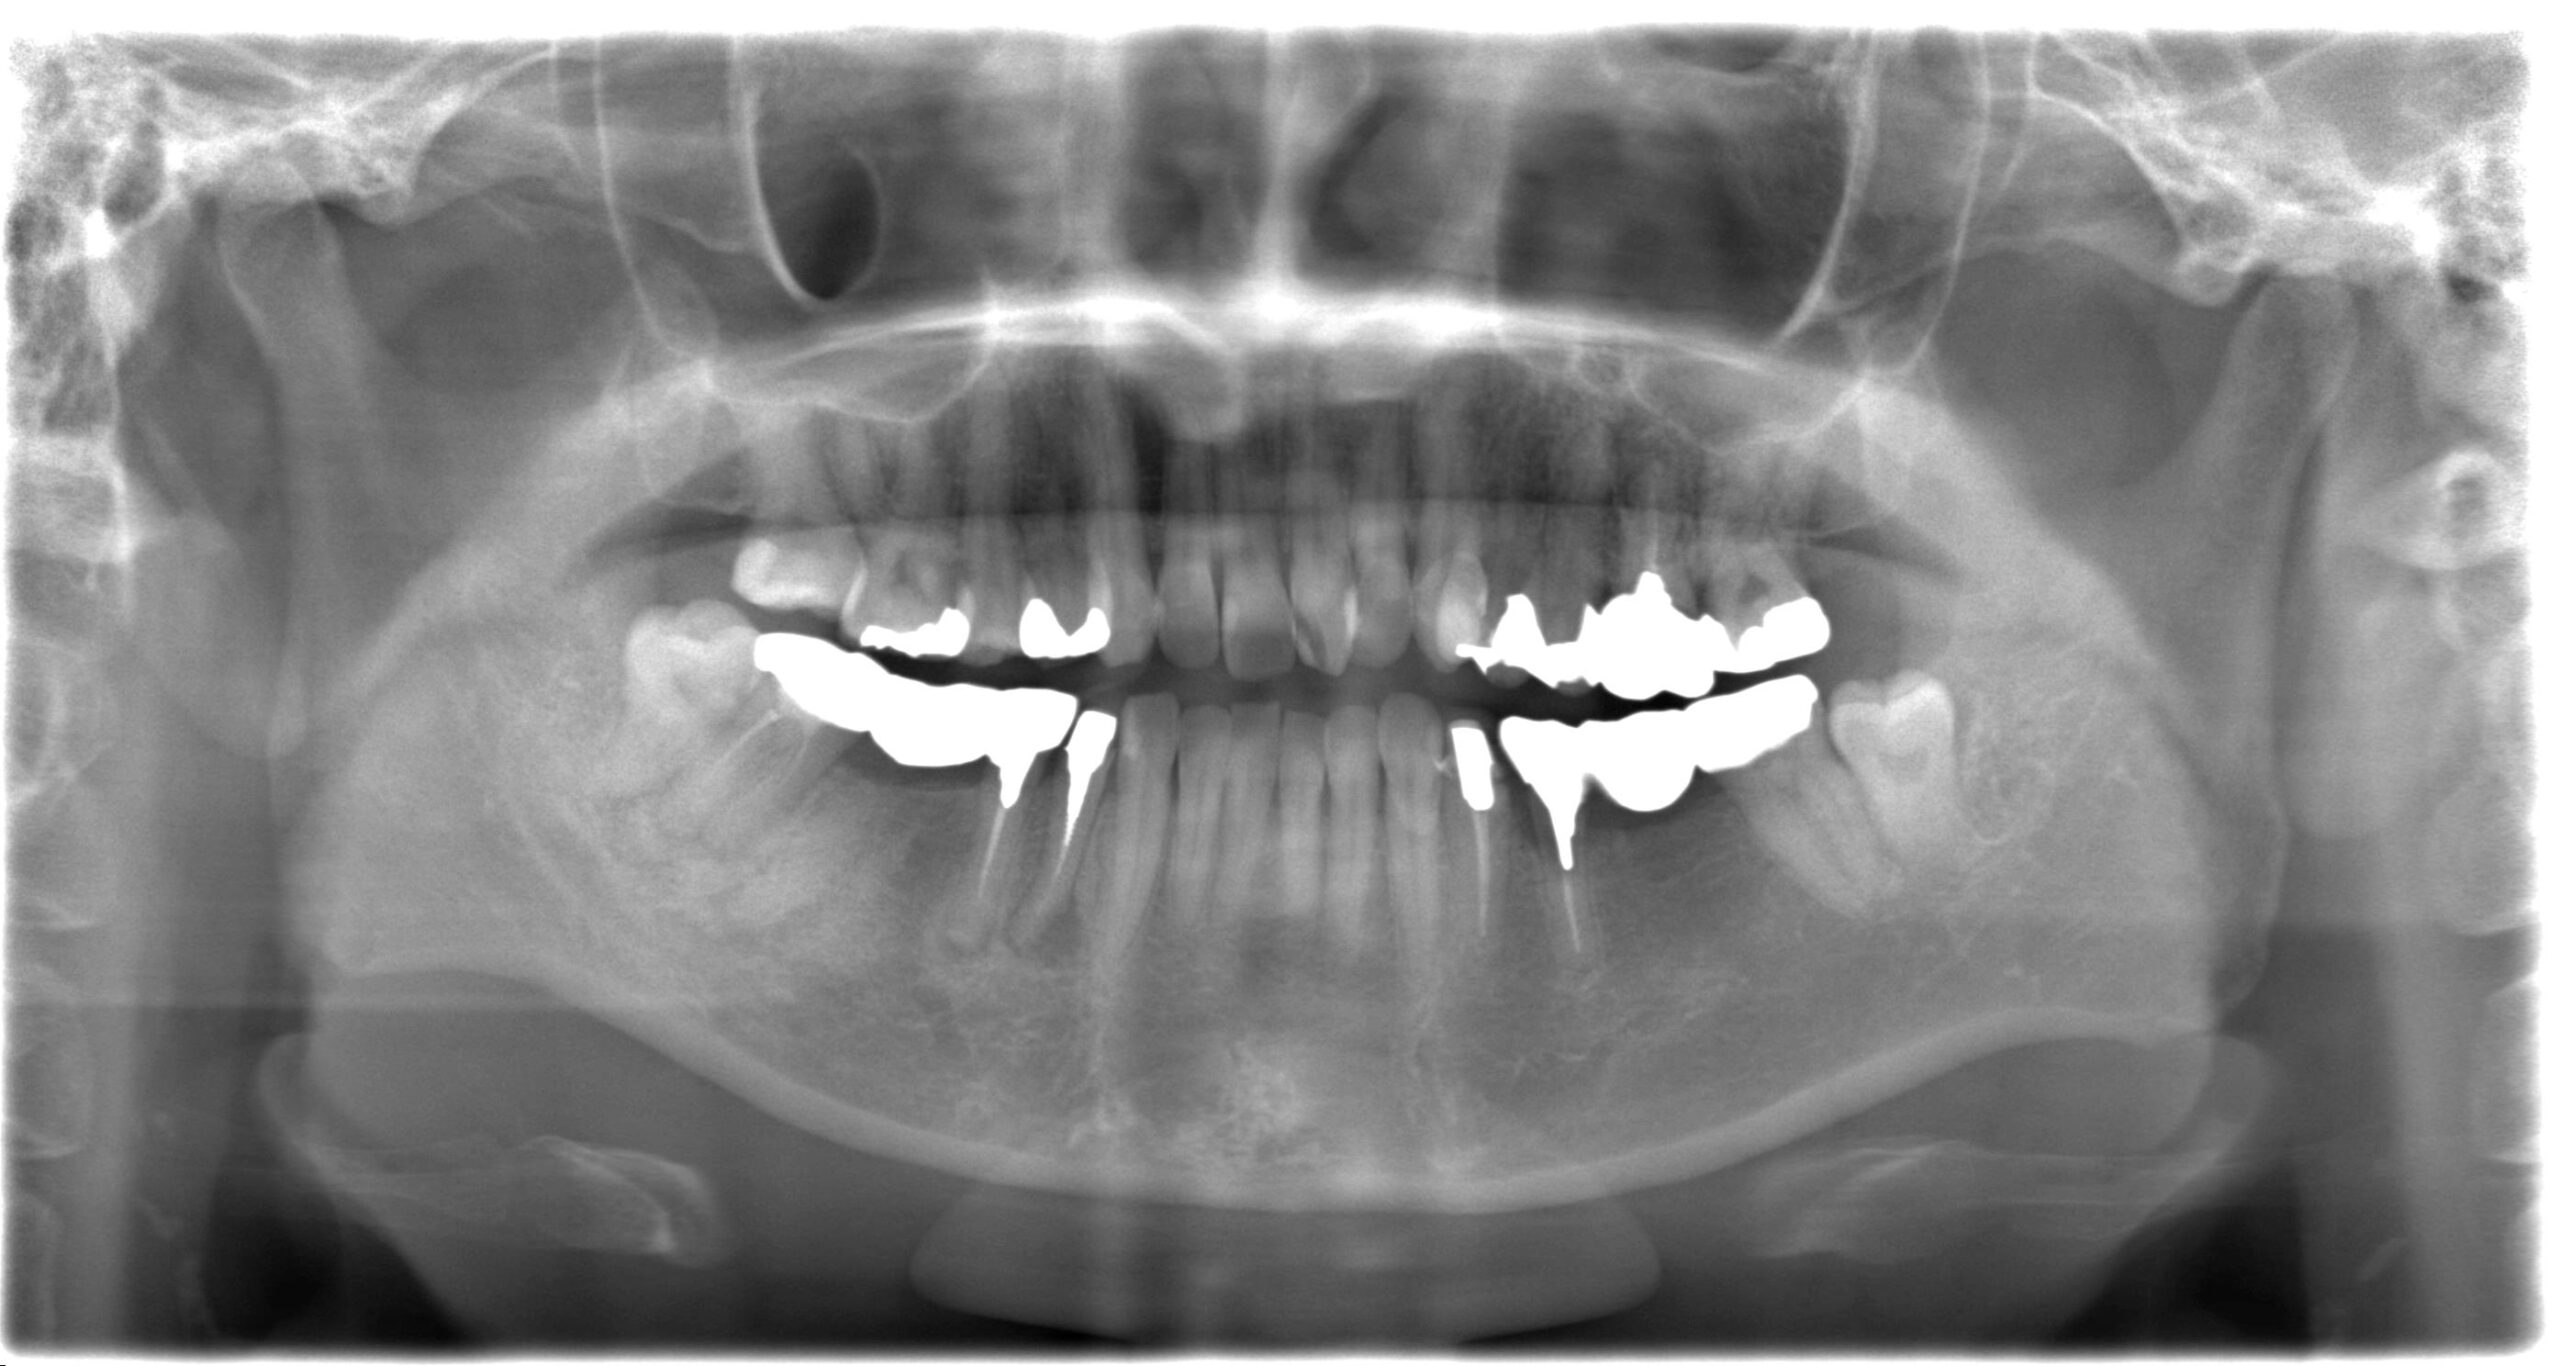

症例01

30代 女性 奥歯を失い歯並びが変わってきた

術前レントゲン

| 主訴 | 奥歯が咬めなくて前歯が出てきた。 奥歯を治療したあと、咬み合わせがもし落ち着いたら前歯も治療したい。 |

| 年代・性別 | 30代 女性 |

| 治療部位 | 下顎両側 67 |

| 治療費用 | インプラント 420,000円×4本 静脈内鎮静法 75,000円×2回 |

| 治療期間 | 10ヶ月 |